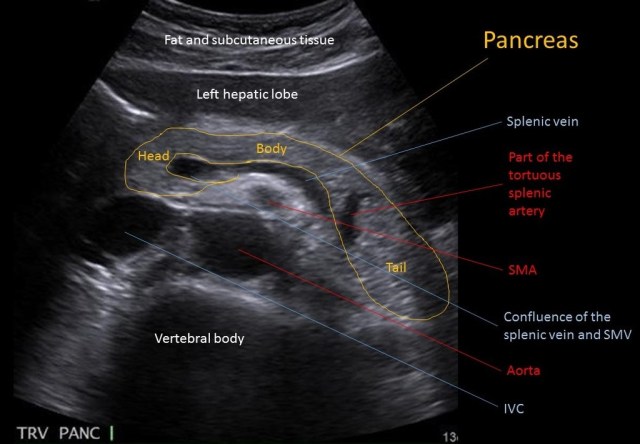

보통 상복부초음파영상에서 췌장을 촬영할 때는 위와 같은 영상을 머리에 떠올리고 촬영하게 됩니다. 새 부리모양의 췌장 두부, 비장정맥(splenic vein)의 앞쪽으로 췌장의 몸통이 위치하면서 췌장꼬리는 비장을 향해 뒤로 꺽이는 모양이 전형적인 양상입니다.

여기서 많은 분들이 착각하는 부분이 췌장꼬리와 비장정맥의 관계입니다. 위의 그림에서도 노란색 글자로 “Tail”이라 표시되어있는 부위를 췌장꼬리라 인식하는 경우가 대부분이고, 대부분의 교과서나 자료들에서도 같은 식으로 묘사하지만 실제로 해당부위가 췌장꼬리인 경우는 거의 없습니다.

이제 다시 위의 초음파 횡단면영상을 보시면, 아니나다를까 췌장 뒤쪽에서 확인할 수 있는 비장정맥이 췌장 몸통부분까지만 확인할 수 있으며, 꼬리(Tail이라고 표시된 부위)라고 표시하고 있는 부위에는 비장정맥이 위치해있지 않고 있습니다. 이 부위가 과연 췌장 꼬리부위가 맞다고 할 수 있으려면 반드시 확인해야 하는 것이 해당부위의 뒤쪽에 왼쪽 콩팥이 위하는지 여부입니다.